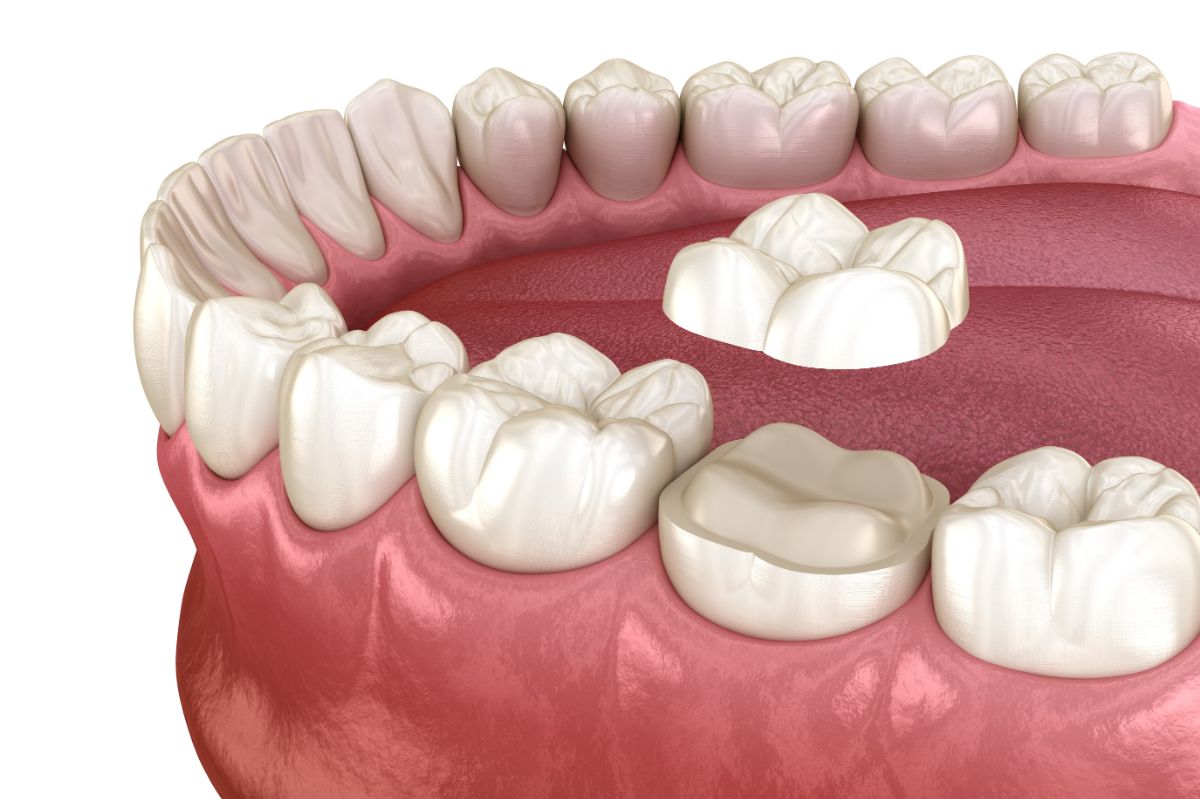

審美治療は、詰め物・被せ物の見た目や材質に配慮しながら、噛みやすさや耐久性も考えて整える治療です。

むし歯治療後、保険診療では金属(いわゆる銀歯)で補うことが一般的ですが、見た目が気になる、金属の素材が気になるといった場合には、白く目立ちにくい素材(セラミックなど)を選ぶ方法があります。

セラミック・

ジルコニア治療の特徴

天然の歯に近く透明感を再現しやすい。

特徴

セラミックよりも硬く、割れにくいため奥歯の治療の選択肢にもなる。

共通するメリットとして、金属を使っていないため、金属アレルギーの方でも選択できる素材であること、密着性が高く、二次むし歯を防ぎやすいことなどが挙げられます。

当院では、ご希望に応じてセラミック、またはジルコニアの詰め物や被せ物をご提案しています。